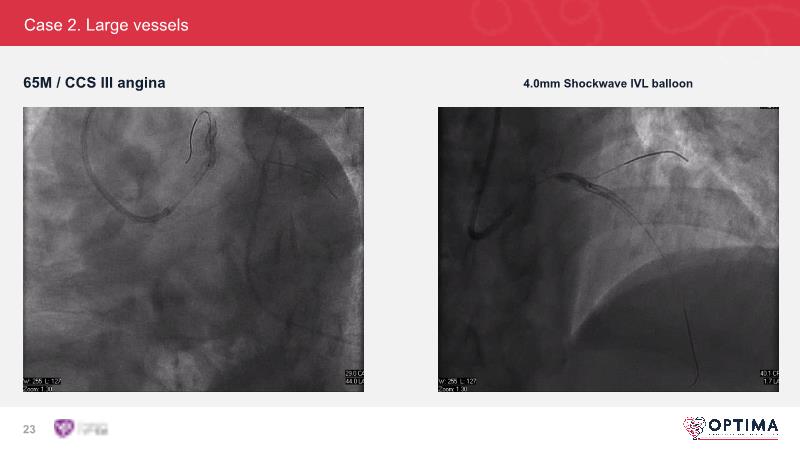

Cracking calcium: intravascular lithotripsy’s unique mode of action in treating calcified lesions – What's the evidence?

Watch this GulfPCR-GIM 2022 session to understand the unique mechanism of action of IVL, the use of intravascular imaging in calcium identification, the gender gap, disrupted CAD trials, and the evolution of treatment of calcified lesions together with the role of IVL.

- To understand the evolution of treating calcified lesions and the role of intravascular lithotripsy